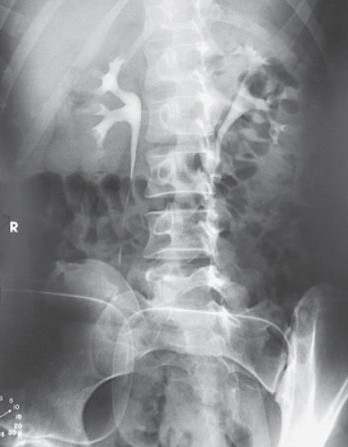

What is this projection

Right lateral

What is this projection and what is the CR angle?

AP axial with CR angled 10-15 degrees caudal

What is this projection?

AP

Left lateral

AP oblique RPO

AP oblique